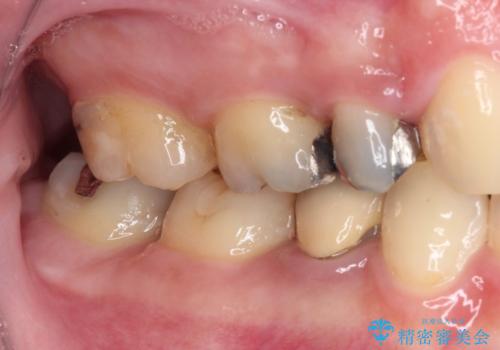

- 他院で抜歯矯正を終えた後、銀色の目立つ奥歯を白くしたいとのことで来院された患者様です。

既にセラミッククラウンが装着されている歯もありますが、不自然な色合いや黒い縁も気になるので、一斉に補綴治療をして統一感を持たせることとしました。

矯正治療を終えたばかりなので、仮歯やセラミッククラウンに置き換えている間に保定がうまくいかなくなる可能性があるため、下顎前歯の舌側を事前にワイヤーで保定しておくこととしました。